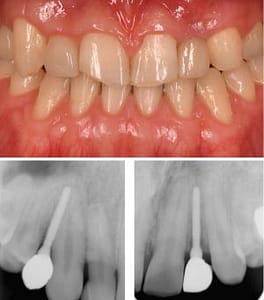

| 主訴 | 上顎前歯および臼歯欠損 |

| 年齢 | 27歳 |

| 性別 | 男性 |

| 治療説明 | 上の歯、2番目の歯(側切歯)と3番目の歯(犬歯)が左右で先天性欠如をしておりました。 矯正治療で、2番3番目の歯の補綴物が入るスペースを確保。 その後インプラントを埋入し、補綴物を装着しました。 前歯部の先天性欠如の場合、骨が薄いケースが多くみられます。 こちらのケースも院長が開発した細いITインプラントを使用します。 |

| 治療期間 | 5ヶ月 |

| 資料提供 | ITデンタルクリニック |